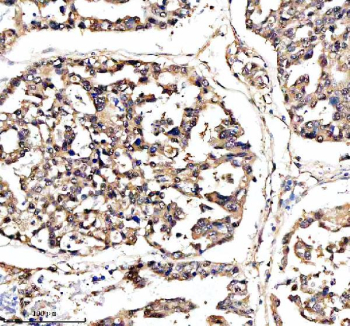

Immunohistochemical staining of DNAJB6 using anti-DNAJB6 antibody. DNAJB6 was detected in a paraffin-embedded section of human lung cancer tissue. Heat mediated antigen retrieval was performed in EDTA buffer (pH 8.0, epitope retrieval solution). The tissue section was blocked with 10% goat serum. The tissue section was then incubated with 2 ug/ml rabbit anti-DNAJB6 antibody overnight at 4oC. Peroxidase Conjugated Goat Anti-rabbit IgG was used as secondary antibody and incubated for 30 minutes at 37oC. The tissue section was developed using an HRP secondary and DAB substrate.